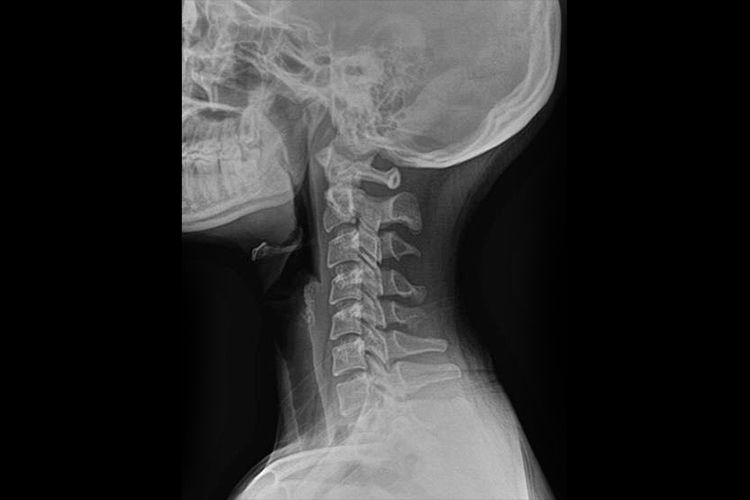

正侧位片图片

颈椎正位片和侧位片的表现不同,具体如下:

颈椎侧位片:椎体呈长方形,上下缘与前后缘成直角,在椎体后方的椎管显示为纵行的半透亮区。椎弓板位于椎弓根与棘突之间,颈椎小关节间隙为匀称的半透明影,颈椎小关节侧位片显示清楚。椎间盘的纤维软骨板、髓核及周围的纤维环系软组织密度,故呈宽度匀称的横行半透明影。